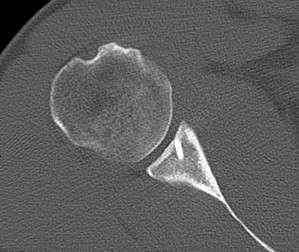

CT

- large Hill Sachs

- large Bony Bankart

Case 2

Recurrent instability

- non recognised bony defect

- revised with Latarjet